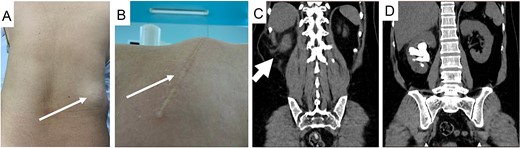

After a thorough assessment, we decided to treat her renal calculi first and deferred treatment of her incisional hernia. A prone mini PCNL was performed using combined ultrasound (US) and fluoroscopy guidance for renal puncture (Fig. 2). After the first session, significant residual stone remained, leading us to perform the salvage PCNL through the original nephrostomy tract and achieve a stone-free result on the C-arm screen. She was discharged on postoperative Day 3 without any complication.

US guidance with carefully exclude bowel during renal puncture (A), real-time US showed the stone and its acoustic shadow (B, arrow), and tract dilation using safety guidewire on fluoroscopy monitor (C).